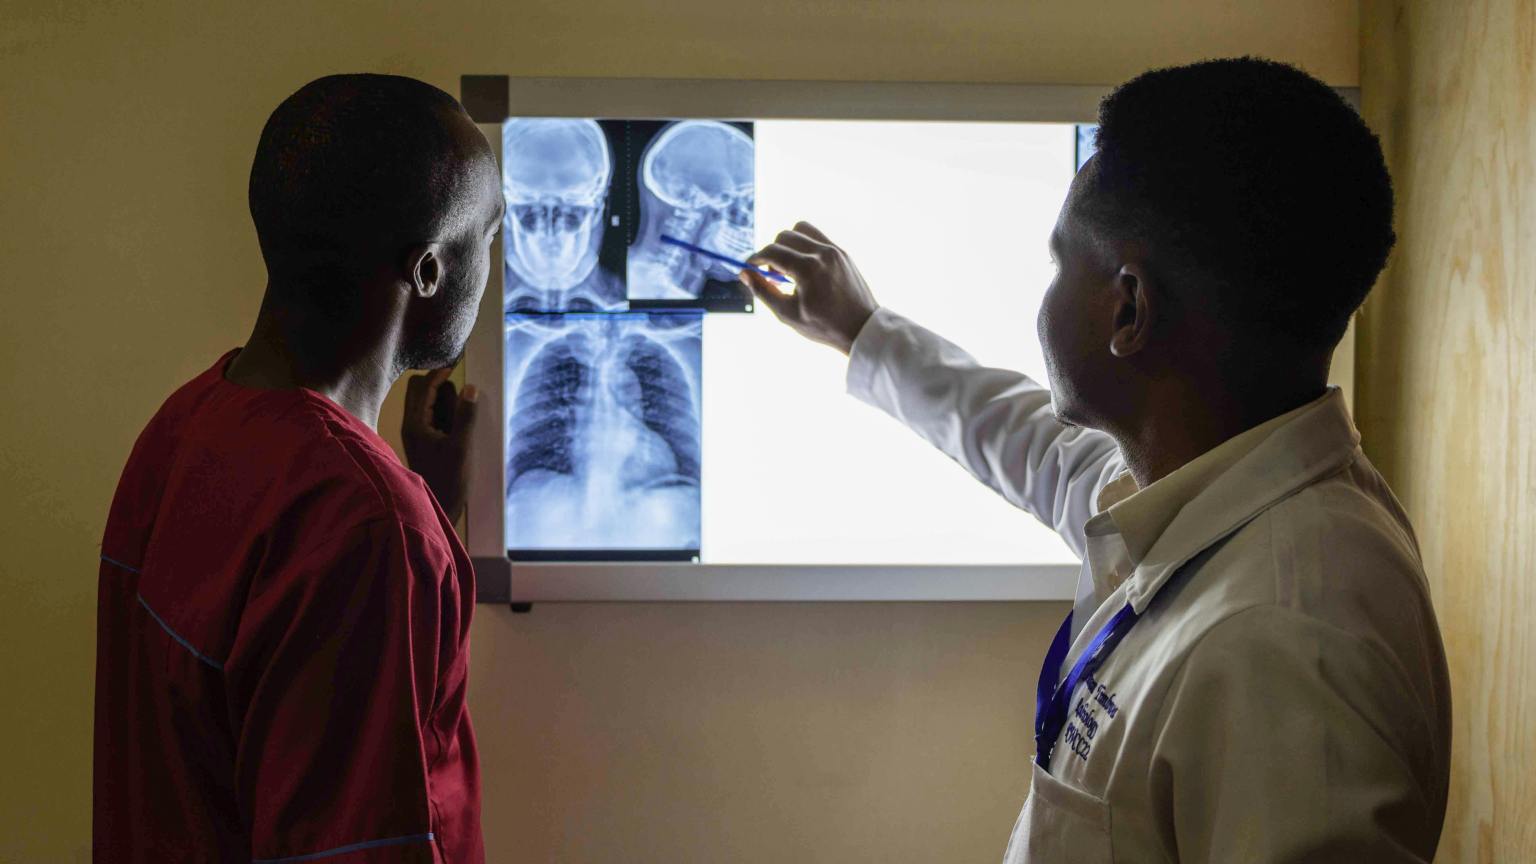

Medical Practitioners' Role

Healthcare providers play a crucial role in determining the necessity and safety of X-ray procedures for patients. They will adhere to referral criteria established by reputable organizations such as the American College of Radiology, the European Society of Radiology, and the Royal College of Radiologists. These criteria help guide healthcare providers in choosing the most appropriate imaging techniques.

Ultimately, medical practitioners will take into account not only the diagnostic value of the procedure but also the associated radiation dose. It is essential for healthcare providers to prioritize patient safety by opting for imaging modalities that minimize radiation exposure whenever feasible. In cases where radiation-based imaging is necessary, medical practitioners strive to use the lowest radiation dose.